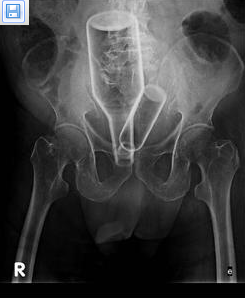

从患者的X光片可明显看到2个瓶子塞入肠道内。

日前澎湖医院急诊室,一名73岁的老者在妻子陪伴下,神色慌张的前往求诊,面对医师询问病情却羞于开口,只是不断表示肚子痛,经过X光照射,赫然发现患者肚中有一大一小的2个瓶子,院长李明杰立即决定全身麻醉,送入开刀房,进入开刀房才发现瓶口接近肛门处,还有绳索相连,旋即决定采用人工拔除方式。

医生小心翼翼,经10余分钟终于取出,小瓶的感冒糖浆玻璃瓶长11公分、直径3.5公分;大瓶的知名提神饮料瓶则长20公分、直径6公分,一次挤入2瓶,连医生都大呼惊奇!因为瓶口处连接绳索,医师研判患者有习惯性塞肛门异物癖,因此也会同身心科协助辅导。加拿大华人网 http://www.sinoca.com/